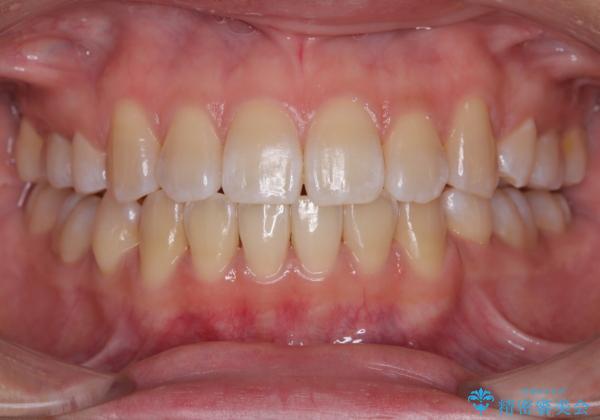

- 上下顎前歯部の非接触(開咬)と下顎のデコボコを主訴に来院された患者様です。

また、開咬を改善するため臼歯部にアンカースクリューを用いて圧下する力をかけていきました。

舌を突出する癖があり、それにより開咬が悪化したり、後戻りの原因になるため、舌のトレーニング(MFT)も行いました。

舌のトレーニングは継続して行ってもらっているため、開咬や抜歯したスペースの後戻りはなく、経過は良好です。